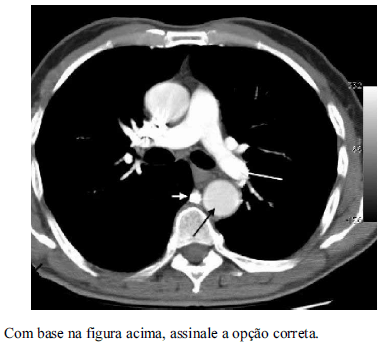

A estrutura anatômica apontada pela seta branca curta em destaque na figura é a artéria pulmonar principal direita.

A seta preta em destaque na figura aponta a aorta ascendente.

A estrutura apontada pela seta branca curta em destaque na figura é a veia ázigo.

Trata-se de exame de ressonância magnética do tórax.

É correto afirmar que não foi utilizado contraste intravenoso nesse exame.